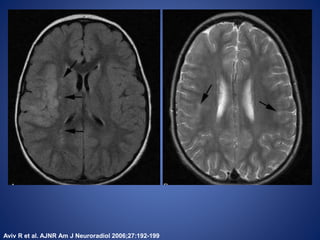

Vasculitis

The distribution of the lesions is most commonly isolated to the

anterior circulation distribution (76%) and is frequently isolated to

the posterior circulation (16%) or involve both anterior and

posterior circulations (11%).

There is overall involvement of gray and white matter but there is a

strong tendency toward central lesions involving the basal ganglia

or lateral lenticulostriate vasculature territory.

The most frequent MRA finding is a benign appearance with

proximal involvement of the carotid termination and proximal ACA

and MCA segments.

Aviv R et al. AJNR Am J Neuroradiol 2006;27:192-199

FLAIR DWI